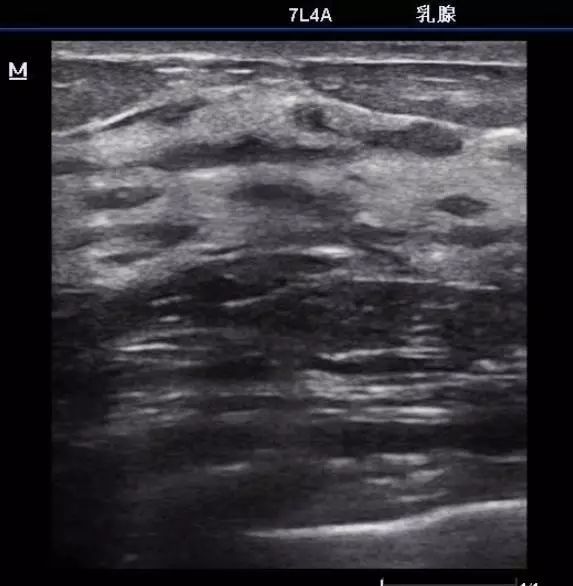

4.囊肿

一层薄薄的皮包着一包水

解读:同样,在超声报告里,对特别典型的“无回声”结节,有经验的超声医师会将其直接判断为“囊肿”,所谓囊肿,可以理解为一层薄薄的皮包着一包水,这在乳腺囊性增生病里较为常见,可以单发,也可以多发。而多数的囊肿是良性、无害的。